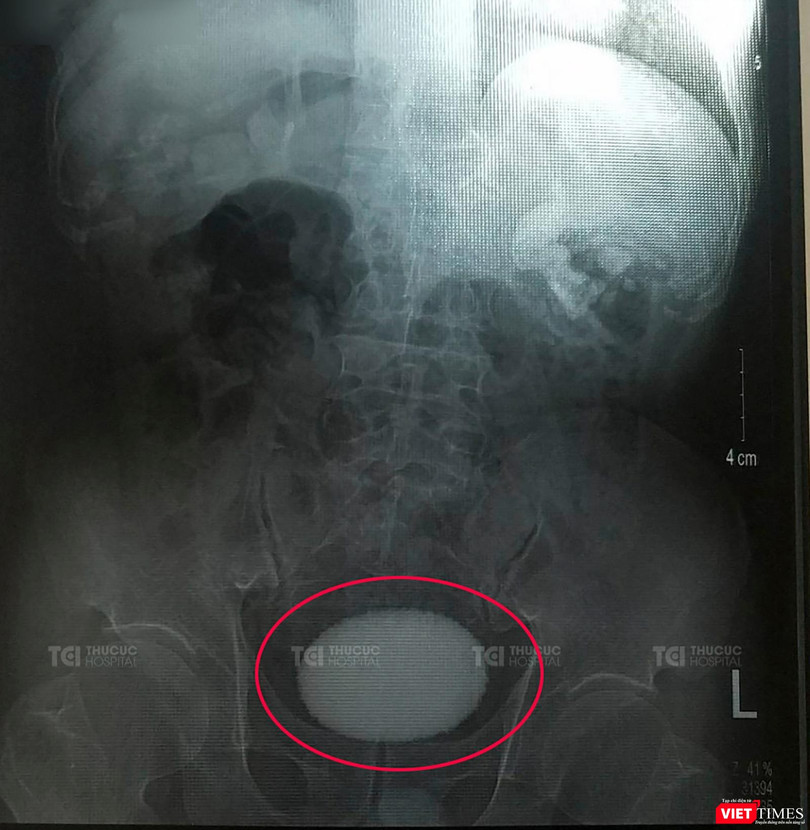

Viên sỏi khủng to bằng quả trứng vịt

Kết quả chẩn đoán hình ảnh cho thấy viên sỏi có kích thước rất to, chiếm gần hết bàng quang. Đặc biệt, viên sỏi còn bám dính rất chặt vào niêm mạc của bàng quang. Sỏi lớn khiến bệnh nhân bị viêm đường tiết niệu dai dẳng và tái đi tái lại không khỏi.

Nhận định trường hợp của anh T. do sỏi to lại dính chặt vào niêm mạc, rất phức tạp, nên các phương pháp tán sỏi nội soi không thể thực hiện hiệu quả được, bác sĩ đã chỉ định phẫu thuật mổ mở để lấy sỏi.